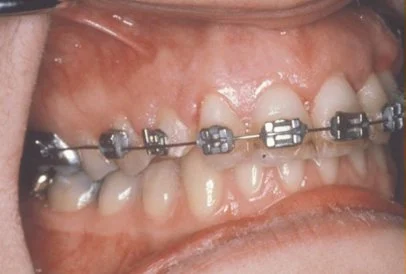

The maxillary cuspid (upper eyetooth) is the second most common tooth to become impacted. The cuspid tooth is a critical tooth and plays an important role in your “bite”. The cuspid teeth are very strong biting teeth and have the longest roots of any human teeth. They are designed to be the first teeth that touch when your jaws close together so they guide the rest of the teeth into the proper bite.

The goal is to erupt the impacted tooth and not to extract it. Once the tooth has moved into its final position, the gum around it will be evaluated. In some circumstances, there may be some minor “gum surgery” required.